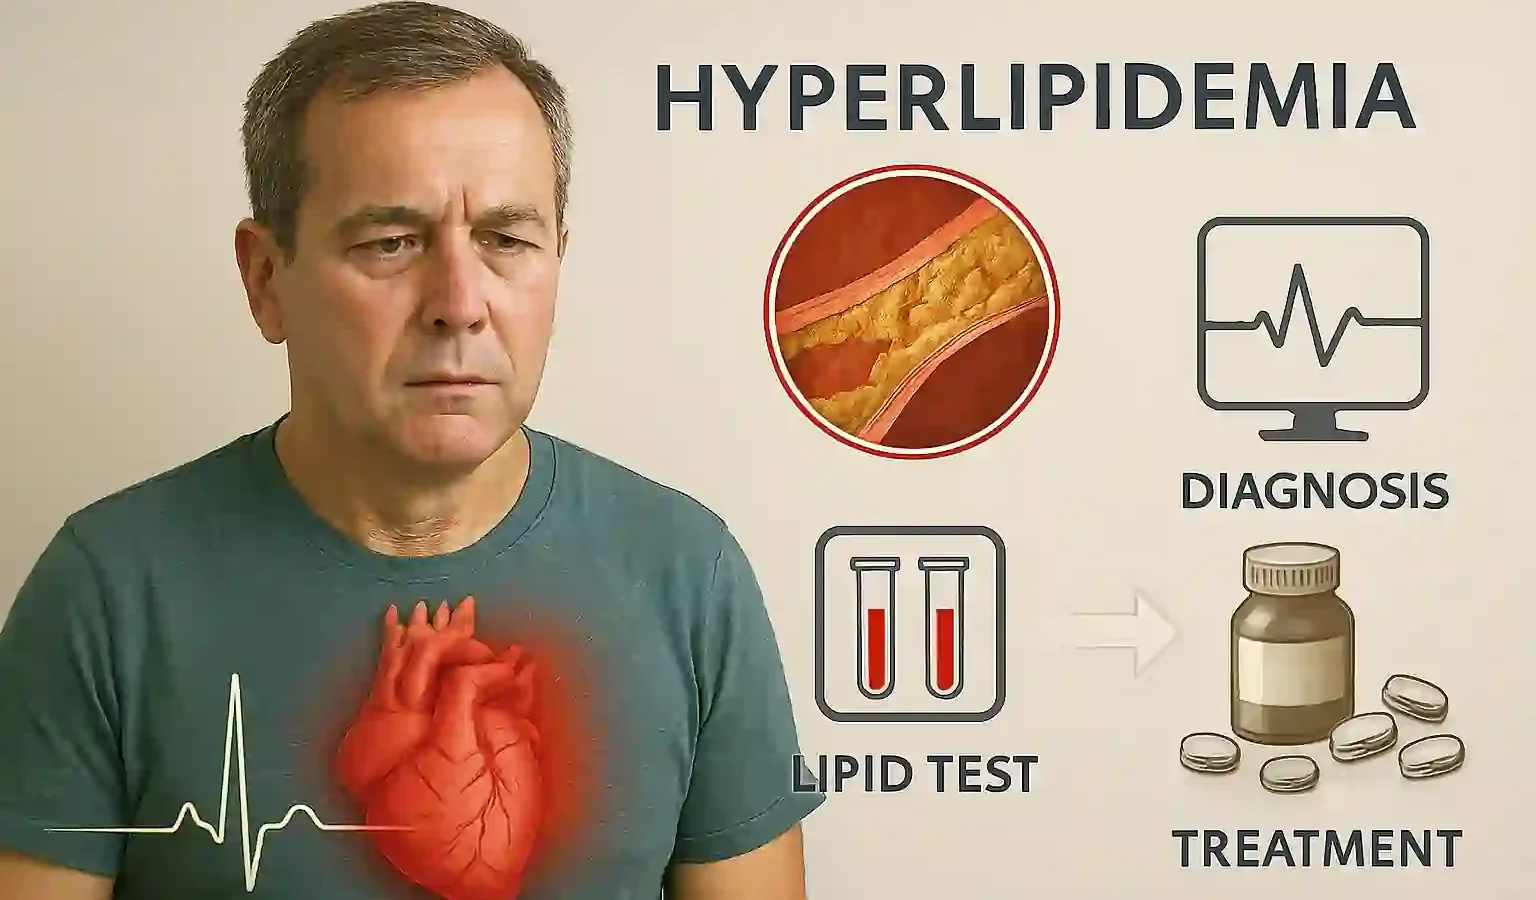

🧬 عوامل خطر آترواسکلروز شامل فشار خون بالا، دیابت، چربی خون بالا، سیگار، چاقی، کمتحرکی و سابقه خانوادگی است. هرچه تعداد عوامل خطر بیشتر باشد، احتمال بروز بیماری نیز افزایش مییابد. کنترل این عوامل نقش مهمی در پیشگیری دارد.

🍔 رژیم غذایی ناسالم، بهویژه مصرف زیاد چربیهای اشباع، ترانس و قندهای ساده، روند آترواسکلروز را تسریع میکند. این مواد باعث افزایش LDL و کاهش HDL میشوند و زمینه را برای تشکیل پلاک فراهم میکنند.

🧪 آزمایشهای خون میتوانند سطح کلسترول، قند خون و سایر عوامل خطر را نشان دهند. این اطلاعات به پزشک کمک میکند تا خطر آترواسکلروز را ارزیابی کند و برنامه درمانی مناسب ارائه دهد. پیگیری منظم آزمایشها اهمیت زیادی دارد.

🩺 تشخیص آترواسکلروز معمولاً با روشهایی مانند سونوگرافی داپلر، CT آنژیوگرافی، MRI یا آنژیوگرافی تهاجمی انجام میشود. این روشها میتوانند میزان تنگی رگ و وضعیت جریان خون را نشان دهند و به تصمیمگیری درمانی کمک کنند.

💊 درمان آترواسکلروز شامل داروهایی برای کاهش چربی خون، کنترل فشار خون و کاهش التهاب است. داروهای استاتین یکی از مهمترین درمانها هستند و میتوانند رشد پلاک را کند کنند یا حتی آن را کوچکتر کنند.